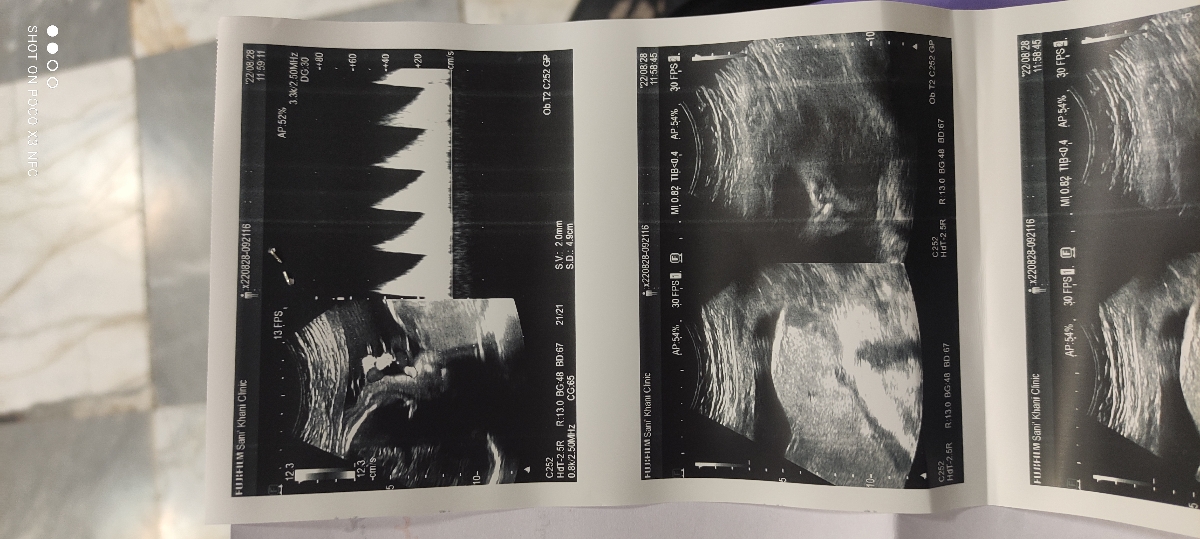

29 هفته و هفت روزم هست ،تحرکات جنین کم شده بود حجم شکمم هم کوچیک شده بود دکتر بیمارستان سونو و نوار قلب نوشتن که انجام بدم.

پزشک اوما

همه چیز در سونوگرافی شما خوب است ،در تست nst عکس کمی ناواضح است نظر خود تیم پزشکی در هنگام انجام nst در این موارد اهمیت دارد چه نظری داشتند؟

تیم پزشکی nst شامل یک پرستار و یک منشی دکتر زنان و زایمان بود که

پرستار گفت خوبه قلبش مشکلی نیست

ولی منشی دکتر گفت تحرکش کمه

توی نیم ساعت دوبار تکون خورد فقط

خواهش میکنم مامان گل ، عزیزم در این موارد باید nst تکرار میشد ایرادی ندارد، شما حتما فردا nst را در بیمارستان تکرار کنید خیالمان از هر جهت راحت شود ، اما نتیجه سونوگرافی عالی است نترسید ❤️❤️